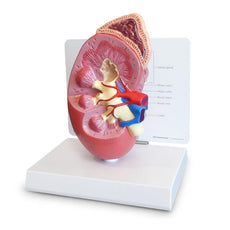

- Kidney with adrenal gland.

One front half of a kidney is removable from the anatomical model of the urinary system. With easy to change male insert (bladder and prostate, front and rear half) and female insert (bladder, womb and ovaries, 2 lateral halves) the Urinary System model is a great teaching tool.